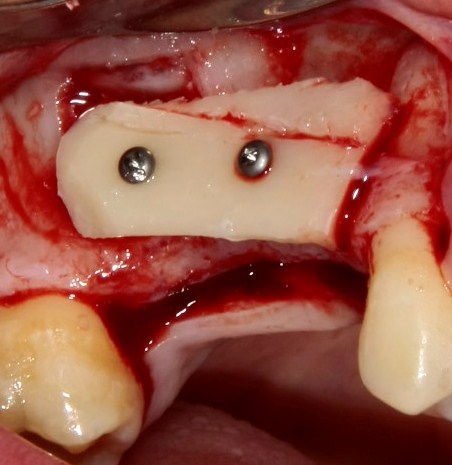

Простой. Надежный. Дешевый. Способ остеопластики.